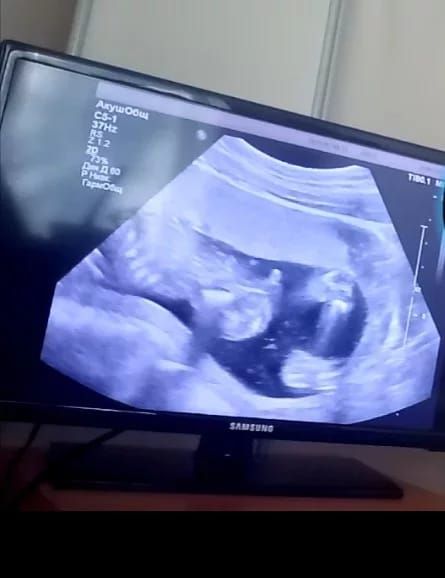

Изображение 19недель по М